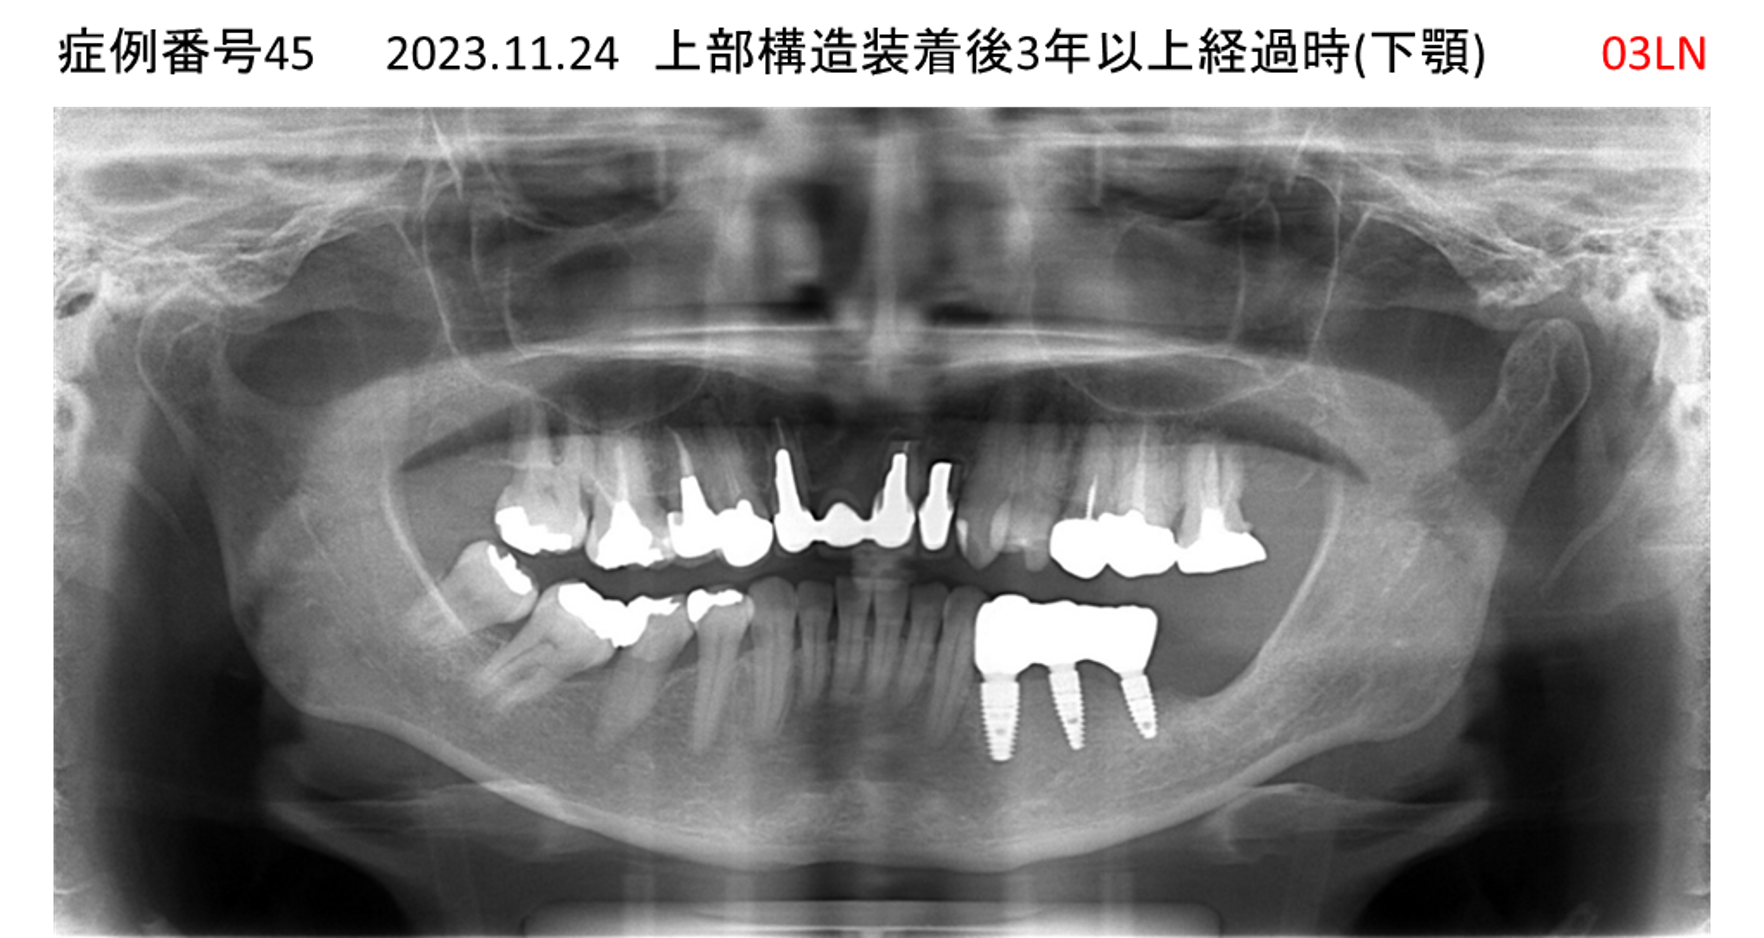

左下の奥歯が痛い患者様のインプラント症例

| 治療名称 |

インプラント |

| 治療費用 |

215万円+税 |

| 治療期間 |

5か月 |

| 患者さんの症状(主訴) |

左下の奥歯が痛い。 |

| 治療内容 |

| 治療結果 |

痛み無く、噛める。 |

| 治療の注意点(リスク/副作用) |

インプラントが壊れたら再治療が必要 |